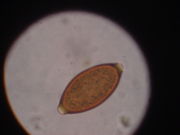

The human whipworm (Trichuris trichiura or Trichocephalus trichiuris), is a roundworm, which causes trichuriasis when it infects a human large intestine. The name whipworm refers to the shape of the worm; they look like whips with wider "handles" at the posterior end.

Infection occurs through accidental ingestion of eggs (which are usually found in dry goods such as beans, rice, and various grains) and is more common in warmer areas. The eggs hatch in the small intestine, and then move into the wall of the small intestine and develop. On reaching adulthood, the thinner end (the front of the worm) burrows into the large intestine and the thicker end hangs into the lumen and mates with nearby worms. The females can grow to 50 mm (2 inches) long. Neither the male nor the female has much of a visible tail past the anus.

Whipworm infestation is detectable by stool examination, which can detect eggs and charcot-leyden crystals. Mebendazole is 90% effective in the first dose, and albendazole may also be offered as an anti-parasitic agent. Adding iron to the bloodstream helps solve the iron deficiency and rectal prolapse.